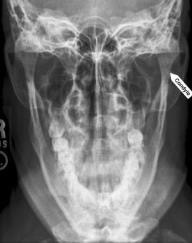

Waters projection

purpose for waters projection

used to evaluate maxillary sinus area